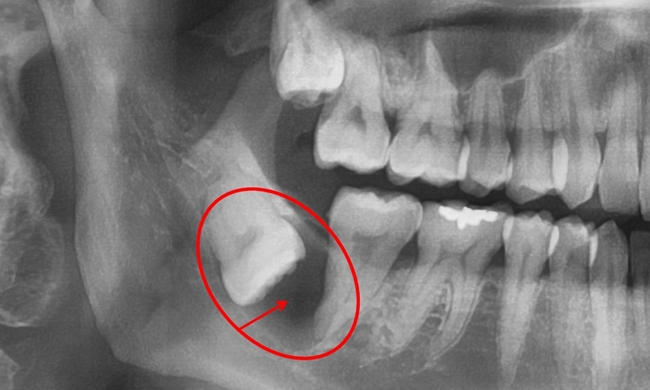

매복사랑니 방치할 경우 ‘함치성낭종’ 생길 수 있어 주의해야

사랑니가 잇몸으로 살짝 덮여 있거나 일부 보이게 되면 증상이 생기는 경우가 많기 때문에 발치하는 경우가 흔하다. 오히려 뼈 속 깊이 묻혀 있을 때 더 큰 문제가 생길 수 있다. 증상이 없어 사랑니가 있는 줄도 모르고 지내다가 우연히 x-ray 사진을 촬영했을 때 사랑니 주위로 물주머니가 있는 것을 발견하기도 하는데 이 물주머니를 ‘함치성낭종’이라고 한다.

사랑니를 포함한 함치성낭종은 처음에는 증상이 거의 없으나 커지게 되면 턱뼈를 점점 녹여 턱뼈를 약하게 하고 치아의 위치를 변화시킬 수 있다. 아주 커지게 되면 약한 충격에도 턱뼈가 부러지는 현상이 발생할 수 있는데, 턱뼈에 생긴 낭종의 크기가 큰 경우에는 전신마취를 하고 낭종 제거와 함께 흡수된 뼈를 보충하기 위한 뼈이식이 필요하다.